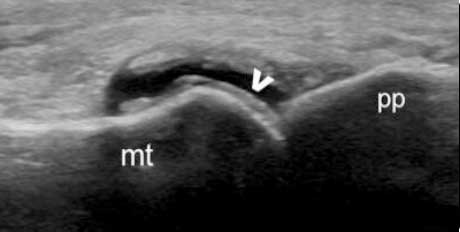

“双轨征”

跖趾关节软骨表面可见高回声不规则增强的软骨滑膜边缘线,呈“双轨征”。

软骨表面回声增强,与深面的骨性关节面强回声线形成“双轨征”。